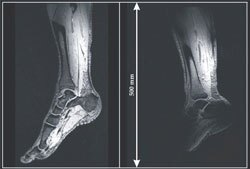

MRI excels at revealing subtle features in soft tissue. Hydrogen nuclei are detected through the electromotive force induced in a nearby coil when their spins flip from an RF pulse. Typically, one coil transmits the pulse and another detects the induced signal. That configuration has been used in clinical settings for decades with imagers built from 1.5 T magnets. In recent years, imagers have been developed with greater field strength to boost sensitivity. But as the field increases, so does the resonance frequency required to excite nuclei. The corresponding wavelength in tissue in a 7-T magnet is about 12 cm, on par with the size of resonator coils that encircle a human head. The result: interference and standing-wave RF patterns. Those inhomogeneities in the RF field are disastrous because they perturb the image contrast between different types of tissue. A group led by Klaas Pruessmann at ETH Zürich has now solved the problem by removing the RF coils entirely and using the conductive lining in a 7-T MRI cavity as a waveguide with an antenna placed at one end. A patient inside the waveguide is exposed to a homogeneous traveling RF wave launched from the same antenna that subsequently detects the spin signals. The in vivo images of a human leg demonstrate that traveling-wave MRI (left) can excite spins more uniformly than can inductive MRI (right). The researchers speculate that, with the tight-fitting induction coils gone, patients may suffer less from claustrophobia and engineers may enjoy more design freedom. (D. O. Brunner, N. De Zanche, J. Frölich, J. Paska, K. P. Pruessmann, Nature 457, 994, 2009 .) — R. Mark Wilson